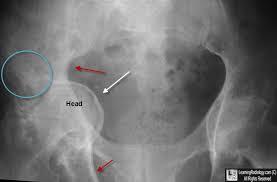

11

Q

[Gen/CT]

Name of anomaly?

Name of syndrome?

Hyperflexibility, MVP, Increased arm to height

A

Dural ectasia

Marfan syndrome